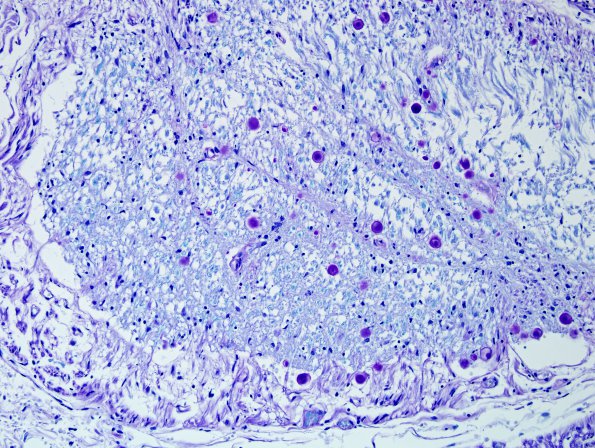

Washington University Experience | BASIC PROCESSES | CNS-PNS Junction | 4C2 Root entry zone (Obersteiner-Redlich zone, Case 4) LFB-PAS 20XA

The majority of this CNS zone involves oligodendroglial myelin with a small rim contributed by the PNS (LFB-PAS)